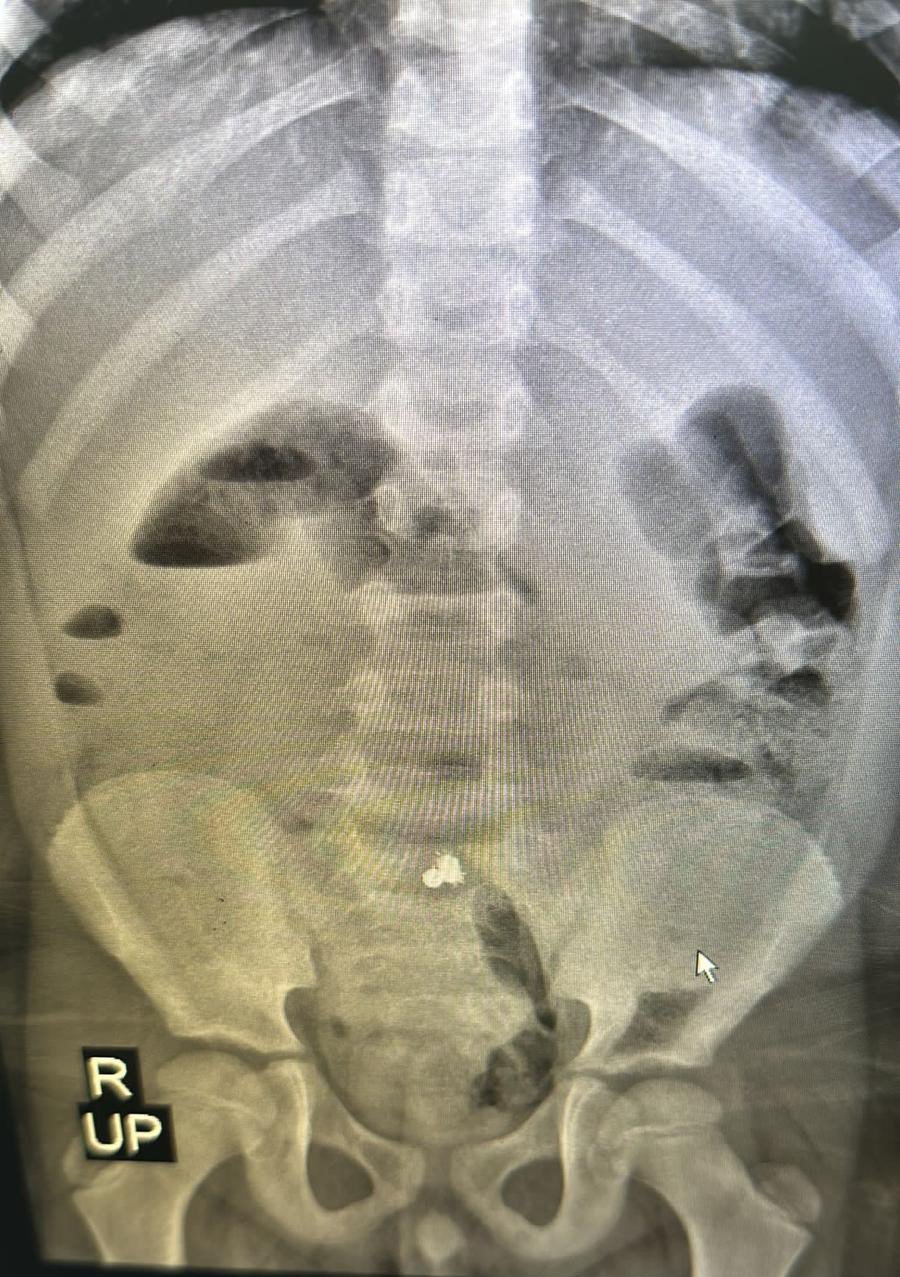

Rize'de yaşayan 7 yaşındaki Miraç Kalay, 11 Nisan Salı günü okulda karın ağrısı şikâyeti üzerine öğretmenleri tarafından babası Orhan Kalay'a (37) haber verildi. Baba oğlunu okuldan aldıktan sonra aile hekimine başvurdu. Aile hekimi yaşanabilecek en ufak sıkıntıda hastaneye başvurmaları gerektiğini aileye belirtti. Daha sonrasında eve giden 7 yaşındaki Miraç, art arda kusmaya başlayınca Rize Devlet Hastanesi acil servis bölümünde tedavi altına alındı. Acil bölümünde yapılan müdahalelerin ardından Miraç'ın midesi için film çekilmek istendi. Çekilen filmin ardından MR'da küçük Miraç'ın mıknatıslı demir bilyeler yuttuğu tespit edildi. Miraç daha sonrasında Recep Tayyip Erdoğan Üniversitesi Eğitim ve Araştırma Hastanesine nakil edildi. 12 Nisan Çarşamba günü saat 08.20 sıralarında ameliyata giren Miraç yaklaşık 1 buçuk saatlik başarılı ameliyatın ardından sağlığına kavuşarak tedavisine devam edilmek üzere serviste gözlem altına alındı. Miraç şimdi ise hastaneden taburcu olmayı bekliyor. Küçük Miraç'ın ameliyatını yapan RTEÜ Eğitim ve Araştırma Hastanesi Çocuk Cerrahisi uzmanı Halil İbrahim Çakmak, ailelerin çocuklarını küçük oyuncaklardan korumaları gerektiğini söyledi.

Büyük bir sıkıntıyı atlattıklarını belirten baba Orhan Kalay, "Mide bulantısı ve kusma şikayetiyle çocuğumuzu hastaneye getirdik. Film çekildi. Filmde görülen objeleri tam tespit edemediği için hocamız MR istedi. MR'da aynı objeler görüldüğü için cerrahımıza haber verildi. Cerrah geldi inceledi. Acilen ameliyat olması gerektiğine karar verdi. Çünkü tespit edilen cisimlerin manyetik top olduğunu belirlediler. Gece 12'de acil bir karar alındı. Sabah 08.20'de ameliyata girdi. Yaklaşık 1,5 saat ameliyat geçirdi ama sağ salim sağlığı yerinde. 1 hafta yeme içme yok. Onun sıkıntısını yaşıyoruz. Sürekli su ve yemek istiyor. Ucuz atlattık. Karnından manyetik top yani mıknatıs çıktı. Bir oyuncak değil de bir obje görüntü olsun diye duruyordu. Çocuklardan uzak tutulması gereken bir şey. Çok tehlikeli bir şey. Bizim çocuğumuz 7 yaşında bi de bunun çocuklara, bebeklere olduğunu düşünmek bile sıkıntılı. Doktorumuzun tavsiyesi de yaş fark etmeksizin büyük objelerle oynasınlar. Ağızlarına veya burunlarına sokabilecekleri oyuncaklardan uzak tutsunlar. Biz sıkıntıyı atlattık. Buradan en azından uyarı niteliği taşısın" diye konuştu.

Evlerde çocukların yutabileceği küçük cisimlerin bulundurulmaması gerektiğini ifade eden Çocuk Cerrahisi uzmanı Halil İbrahim Çakmak ise "Hastamız 7 yaşında erkek bir hasta. Karın ağrısı şikayetiyle acil servise başvuruyor. Hastamızın acilde çekilen filminde manyetik özelliği olan metalik bir cisim yuttuğu görülüyor. Yapılan incelemede bağırsaklarda delinme olduğu obje yuttuğu görüldü. Acil şekilde ameliyata alındı. Ameliyatta yuttuğu objenin manyetik özelliği olan 3 obje olduğu ve bağırsağı 3 yerden deldiği gözüktü. Şu anda sağlığına kavuşturuldu. Bu tip oyuncakları, objeleri evde bulundurmamak gerek. Çünkü bağırsak delinmesi hayati tehlike oluşturan bir durum. Bu bakımdan evimizde çocukların yutabileceği boyutta oyuncakları bulundurmayalım" şeklinde konuştu.